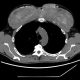

سیتیاسکن قفسه سینه یک مرد، مناطقی بسیار روشن را نشان داد که بیانگر رسوب کلسیم در عضلات سینه او بود. این نقاط دقیقاً همان جاهایی بودند که وی پیشتر روغنهای حجمدهنده عضلانی را تزریق کرده بود.